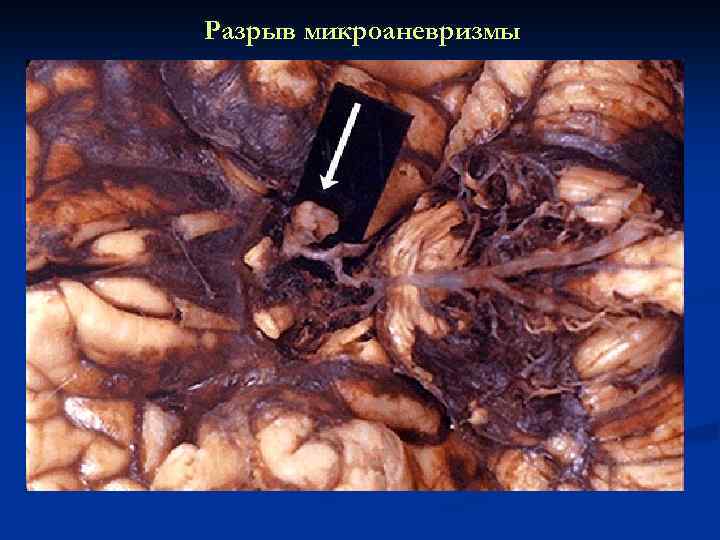

Кровоизлияние Разрыв

Приобретённые «ягодные» микроаневризмы при ГБ

Разрыв микроаневризмы